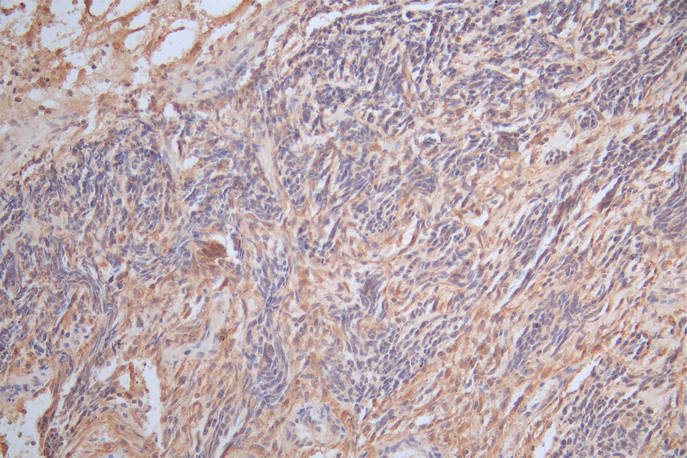

IHC image of CSB-RA009369MA1HU diluted at 1:300 and staining in paraffin-embedded human glioma cancer performed on a Leica BondTM system. After dewaxing and hydration, antigen retrieval was mediated by high pressure in a citrate buffer (pH 6.0). Section was blocked with 10% normal goat serum 30min at RT. Then primary antibody (1% BSA) was incubated at 4°C overnight. The primary is detected by a Goat anti-Mouse IgG labeled by HRP and visualized using 0.05% DAB.